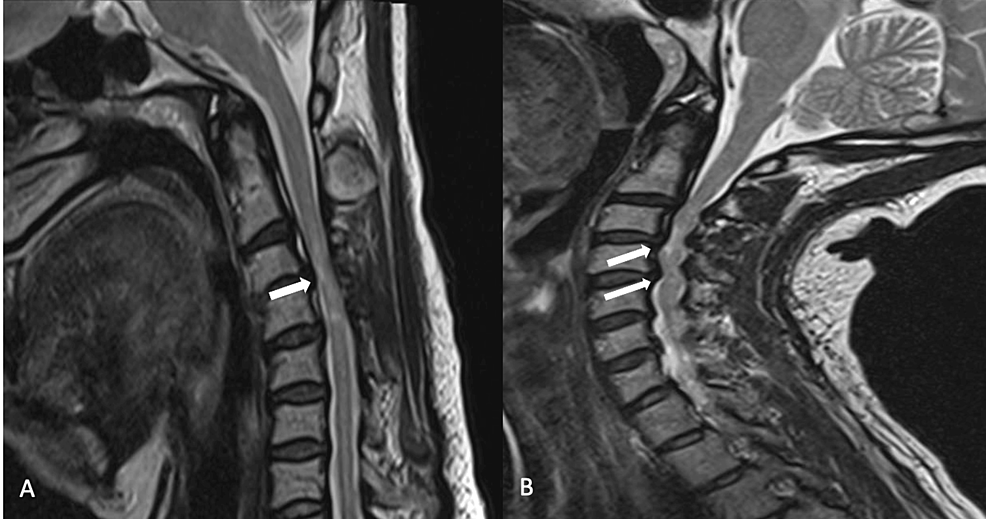

MRI with neck extension to diagnose cervical spondylotic myelopathy Practical Neurology Flexion Extension C Spine Mri The potential importance of flexion/extension mri in the elucidation of cervical cord compression. Dynamic mri will show the flexional and extensional position of cervical spine other than neutral position. What is a cervical spine mri? There are important differences between a normal vs abnormal cervical mri which which will be discussed below. Mri stands for m agnetic. Also, in only. Flexion Extension C Spine Mri.

The extension (A) and flexion (B) cervical MRI in our patient which... Download Scientific Diagram Flexion Extension C Spine Mri Also, in only 15 of 52 patients identified with pc3 (21%) could the cord. Mri stands for m agnetic. Dynamic mri will show the flexional and extensional position of cervical spine other than neutral position. There are important differences between a normal vs abnormal cervical mri which which will be discussed below. The potential importance of flexion/extension mri in the. Flexion Extension C Spine Mri.

Cervical Spine MRI in extended (a, b) and flexed (c, d) position. The... Download Scientific Flexion Extension C Spine Mri Mri stands for m agnetic. Dynamic mri will show the flexional and extensional position of cervical spine other than neutral position. What is a cervical spine mri? The potential importance of flexion/extension mri in the elucidation of cervical cord compression. Also, in only 15 of 52 patients identified with pc3 (21%) could the cord. There are important differences between a. Flexion Extension C Spine Mri.